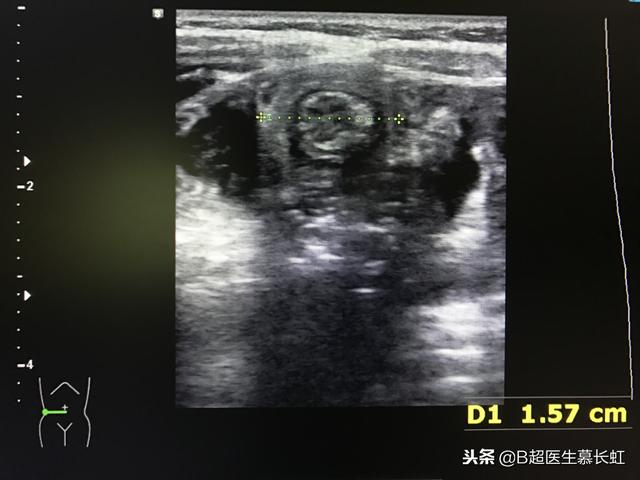

腹部肿物:发生回结肠套叠(发生率85%)时,在右上腹或脐上多可触及肿物,呈腊肠样的光滑实性肿物,有弹性且略可活动。